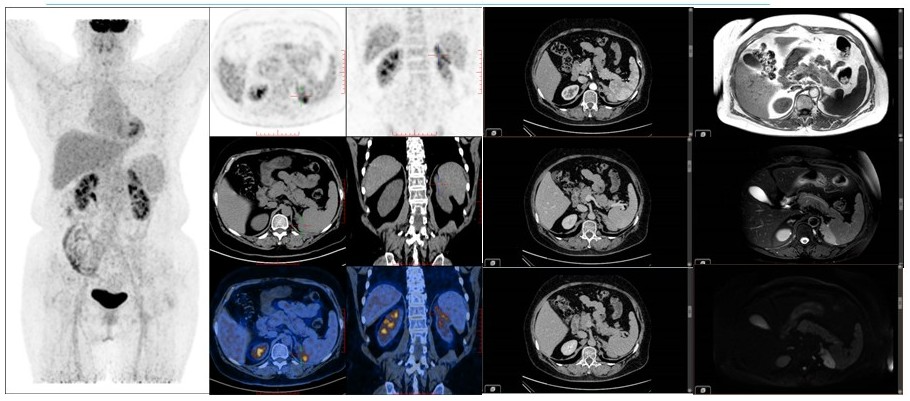

病例(14为一老年女性,体检发现左肾上腺肿物就诊增强CT检查示左侧肾上腺区不规则团片状软组织密度灶,增强扫描呈轻度强化,MRIT1WI低信号、压脂T2WI稍高信号、DWI高信号;18F-FDG PET/CT示肿物代谢轻度不均匀增高;(左肾上腺肿物)切除病理为结外边缘区淋巴瘤

14. 63岁,检查发现左肾上腺肿物1月余边缘区淋巴瘤